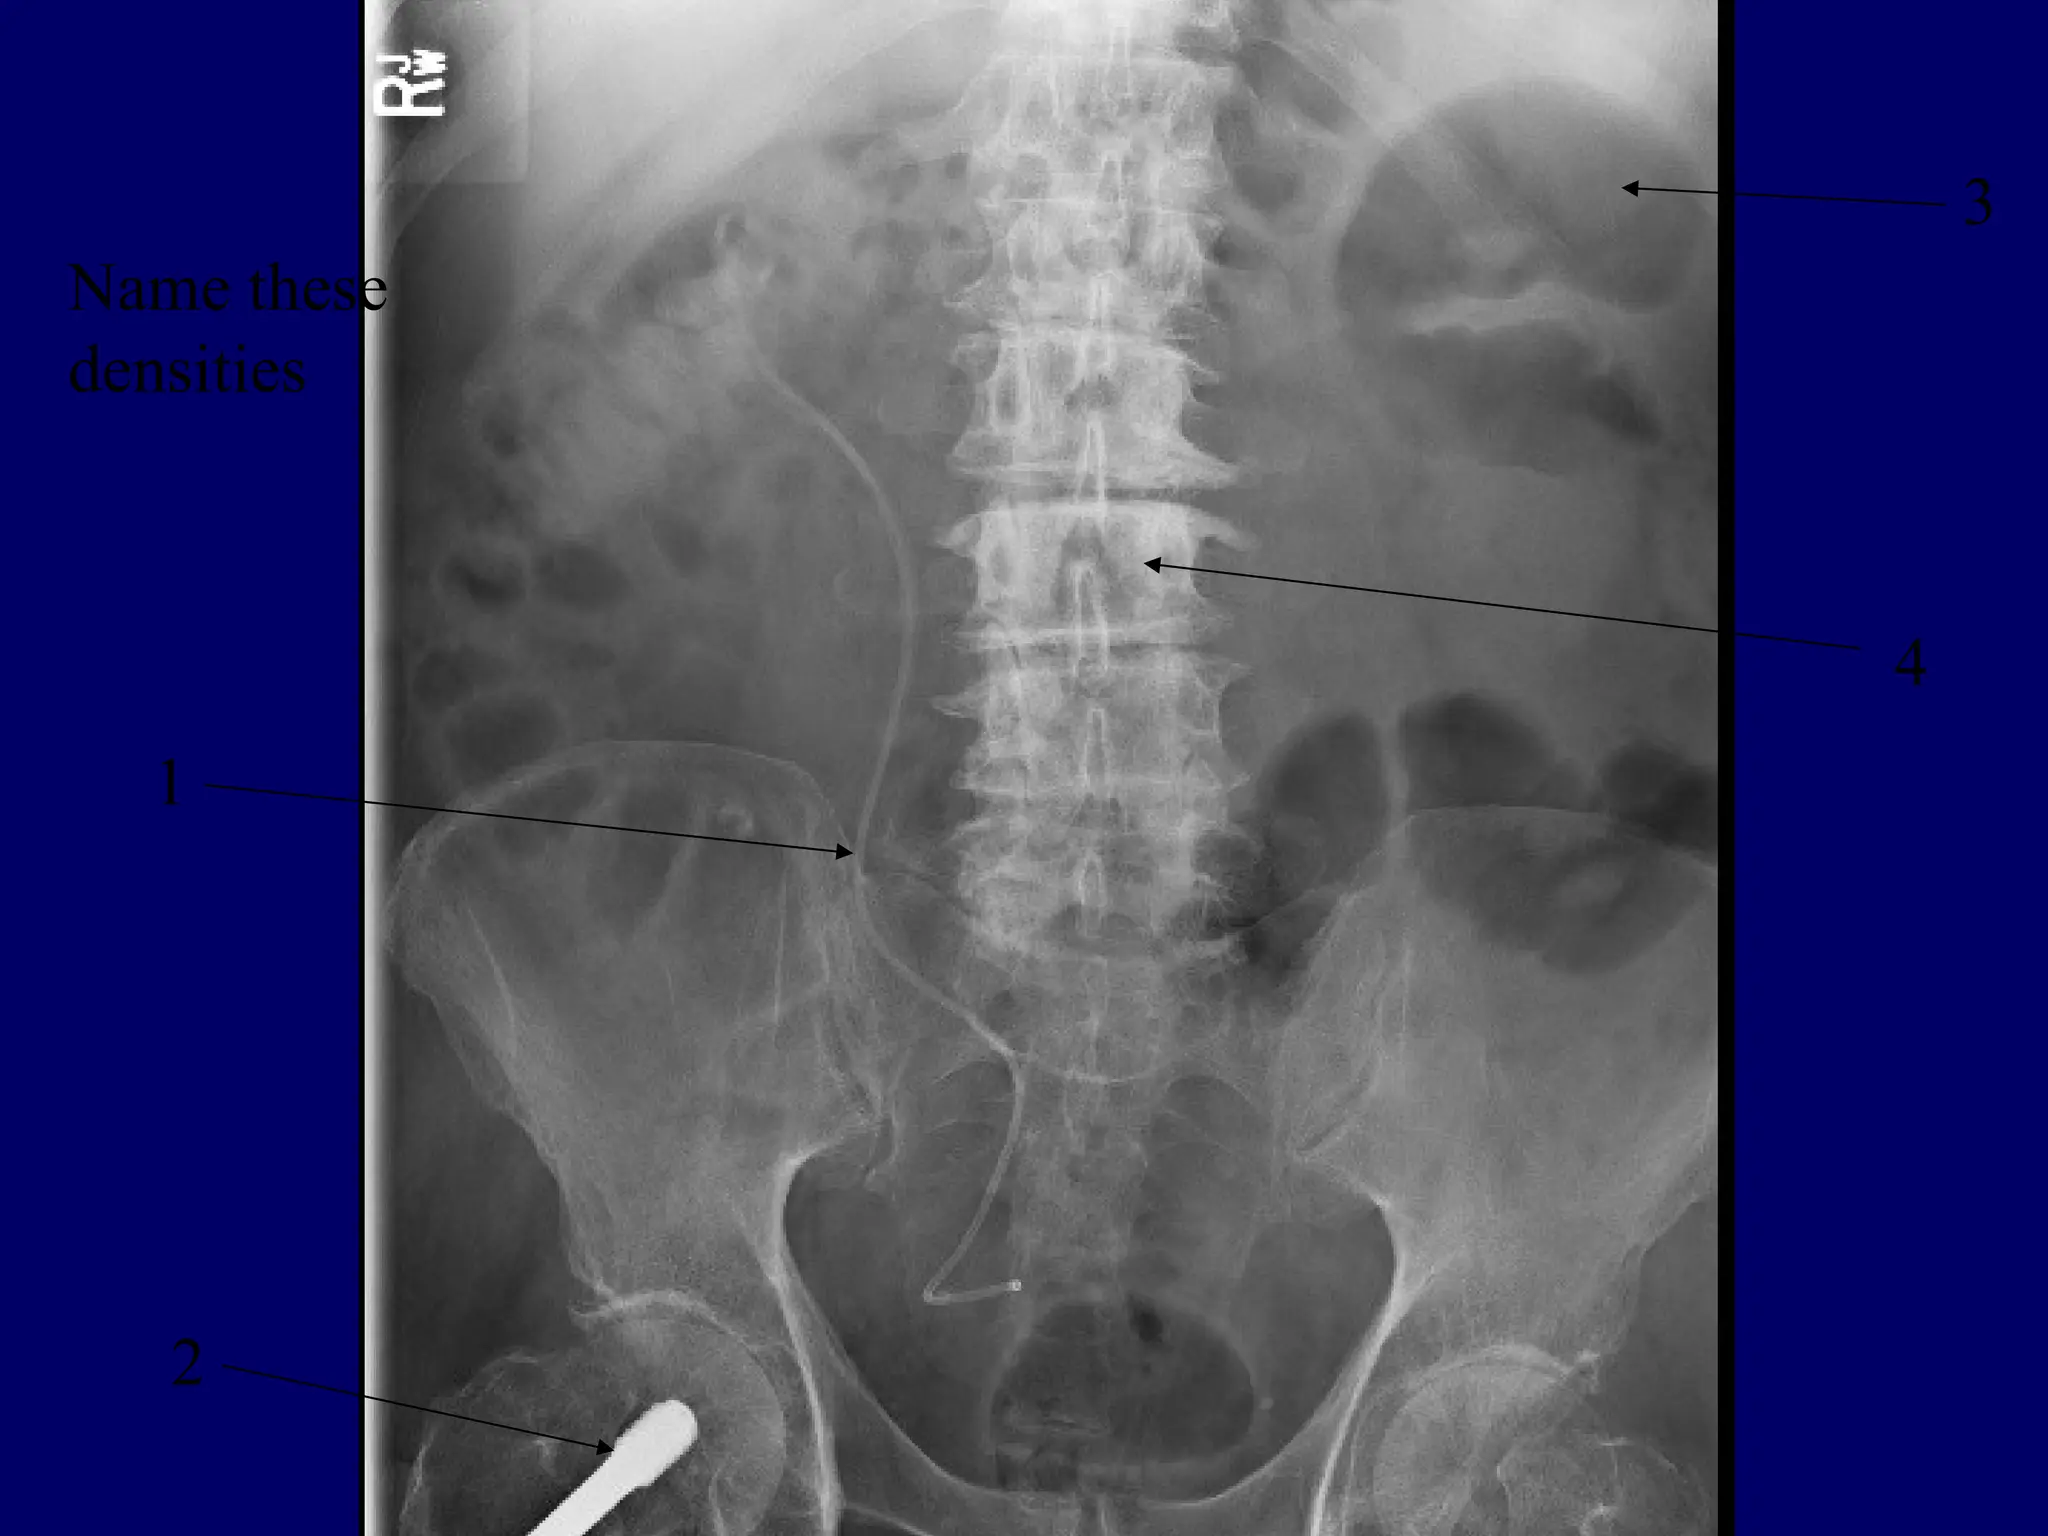

5 Basic Radiographic

Densities

 Air

 Fat

 Soft tissue/fluid

 Mineral

 Metal

Name these radiographic densities.

Radiographic Opacities

 Metal White

 Mineral – Bone Light grey

 Soft tissue – fluid Grey

 Fat Dark grey

 Air Black